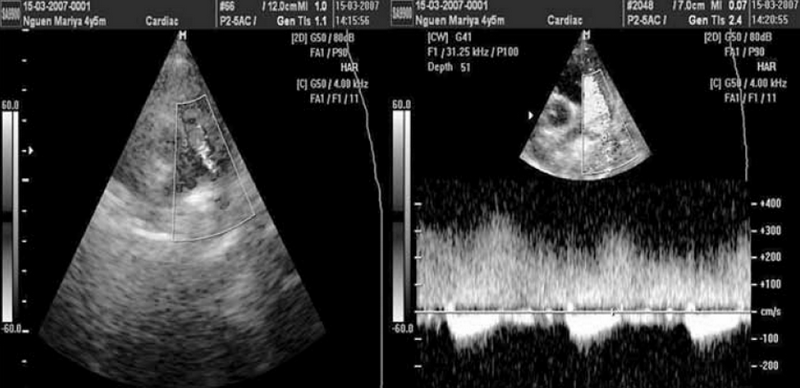

Аускультативная картина у обследованных детей с ОАП была чрезвычайно разнообразной (табл. 2). Классический машинный систоло-диастолический шум был выявлен лишь у 13 детей с ОАП (15 % от общего числа) (рис. 2).

Рис. 2. Исследование выполнено из левой парастернальной позиции по короткой оси. В зоне интереса ствол легочной артерии в режиме цветного допплеровского картирования. В синих тонах кровоток в легочной артерии «от датчика», в красных тонах кровоток через открытый артериальный проток «к датчику». Справа — допплерография в стволе легочной артерии — диагностируется систоло-диастолический сброс через открытый артериальный проток, сопровождающийся «машинным» шумом

У 70 % детей выявлялся лишь систолический шум во 2–3-м межреберьях слева у грудины, сопровождавшийся у половины из них акцентом 2-го тона над легочной артерией. Еще 15 % детей с ОАП вообще не имели значимых шумов над областью сердца (см. табл. 2).

В подавляющем большинстве случаев сброс крови из аорты в легочную артерию через ОАП визуализируется в стволе легочной артерии как поток красного спектра, направленный к датчику в левой парастернальной позиции по короткой оси (см. рис. 2). Сложности эхокардиографической диагностики и дифференциальной диагностики ОАП у детей могут быть обусловлены наличием других разнонаправленных потоков, визуализируемых в стволе легочной артерии, особенно в режиме цветового допплеровского картирования (рис. 3–6). Часть из них направлена «к датчику» и окрашивается в красные цвета, другие направлены «от датчика» и визуализируются как потоки синего цвета. Таким образом, высокоскоростные патологические потоки из аорты в легочную артерию через открытый артериальный проток и аортолегочную фистулу имеют направление «к датчику» и окрашиваются в цвета красного спектра. Низкоскоростные потоки из бассейна коронарных артерий в легочную артерию через коронарные фистулы чаще окрашиваются в синие цвета «от датчика» (см. рис. 3–5).